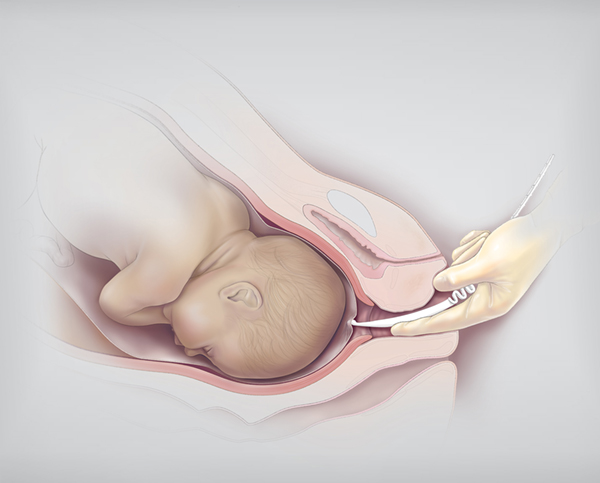

Многоводие при беременности: симптомы и лечение